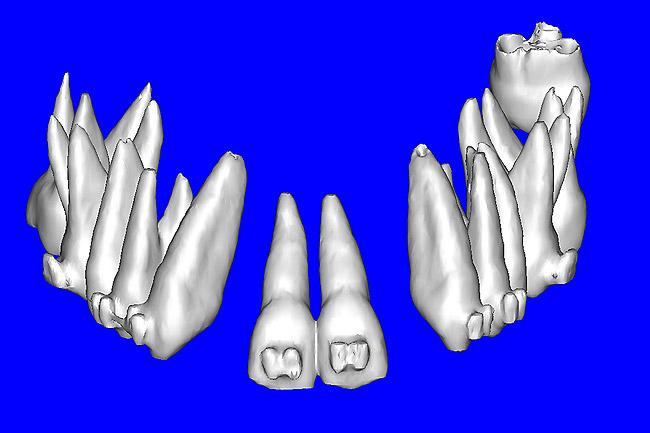

Using different masking (segmentation) and threshold Hounsfield unit values, several new 3D bone volumes can be created which offer invaluable information. To help determine the final position of each implant a new bone model was created with a Hounsfield unit value of 1480, which eliminated all but the densest objects included in the scan data. (Results may vary depending on the CBCT machine used.) The inner and outer layers of bone were removed, leaving the underlying enamel and root structure of the teeth (Figure 8A). After the bone had been stripped away, the root inclinations were examined closely. The most striking findings confirmed the rotated position of the right central, while revealing the slight mesial dilaceration of the root apex, which converged on the space needed for the path of the potential implant (Figure 8B). The schematic shapes of the proposed implants were visualized for the right and left lateral spaces in different rotations of the 3D maxillary arch. It was at this point that a determination was made as to the appropriate implant shape and type that would fit the available space while avoiding encroachment on adjacent tooth roots. A tapered design implant (Tapered Screw-Vent®, Zimmer Dental, www.zimmerdental.com) was chosen from the large virtual library. With the SIMPlant software, the virtual library contains data from dozens of implant manufacturers and realistic.computer-aided design representations as seen in Figure 9A through the translucent bone. The position of the left implant can be visualized with adequate mesial-distal distance between adjacent tooth roots (Figure 9B) and a more delicate placement (Figure 9C).

Figure 8a  By using the masking feature, the inner and outer layers of bone were removed virtually, revealing (A) the enamel and root structure of the teeth and the rotated position of the right central and (B) a slight mesial dilacerations of the root apex.

Figure 8a

Figure 8b  By using the masking feature, the inner and outer layers of bone were removed virtually, revealing (A) the enamel and root structure of the teeth and the rotated position of the right central and (B) a slight mesial dilacerations of the root apex.

Figure 8b